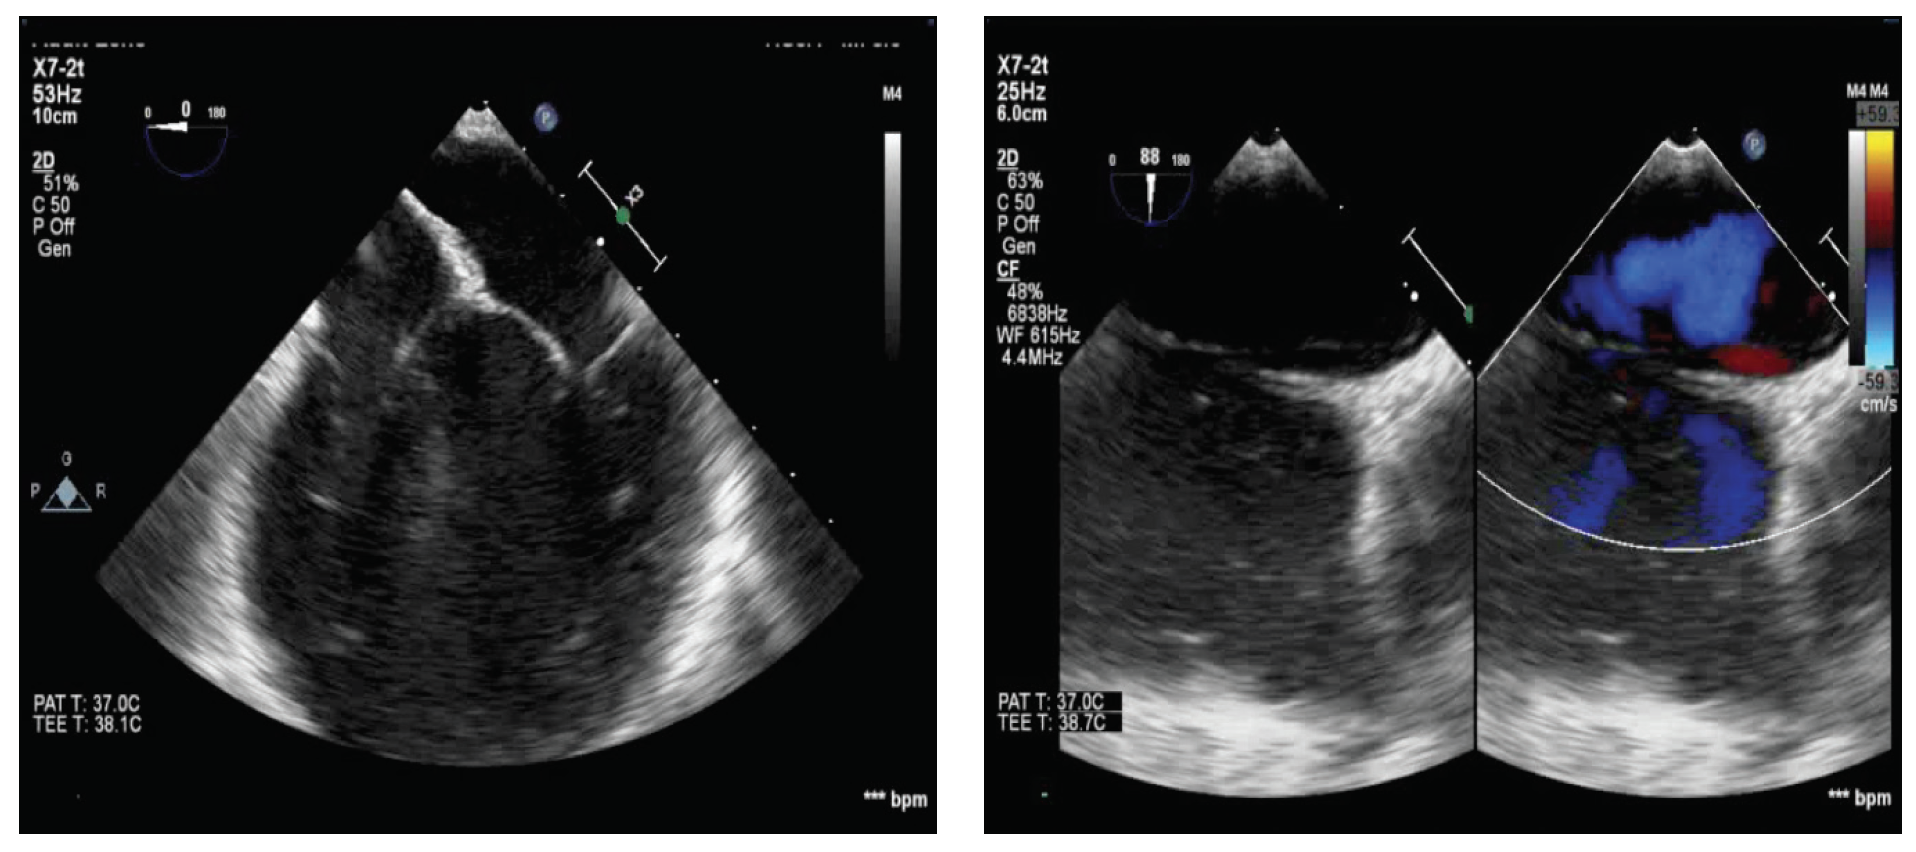

The initial workup shows no arrhythmia on 7-day Holter monitoring. The results of echocardiography were normal, and the finding of a thrombophilia test was negative. Brain imaging showed no cause in the carotid or vertebral circulation. The results of baseline transesophageal echocardiography (TEE) show a long tunnel–type patent foramen ovale (PFO) with an atrial septal aneurysm (Figure 1). A bubble study during TEE confirmed the PFO with a grade 3 shunt.

Figure 1. Baseline TEE demonstrating a PFO with an atrial septal aneurysm.